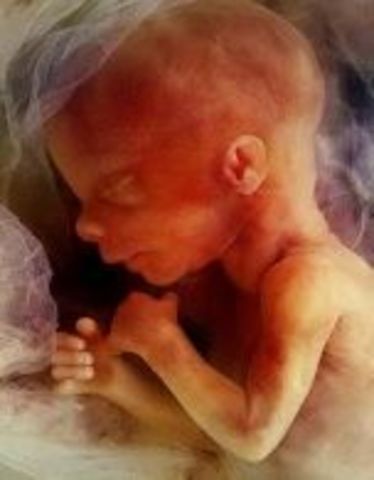

• Week 9: Fingers and Toes Form

Week 9: Fingers and Toes Form

Many more body parts are forming such as the tongue, the bones, eyelids, etc. The fingers and toes are the most defined. The baby is developing in a little bag of fluid which it is swimming around in.